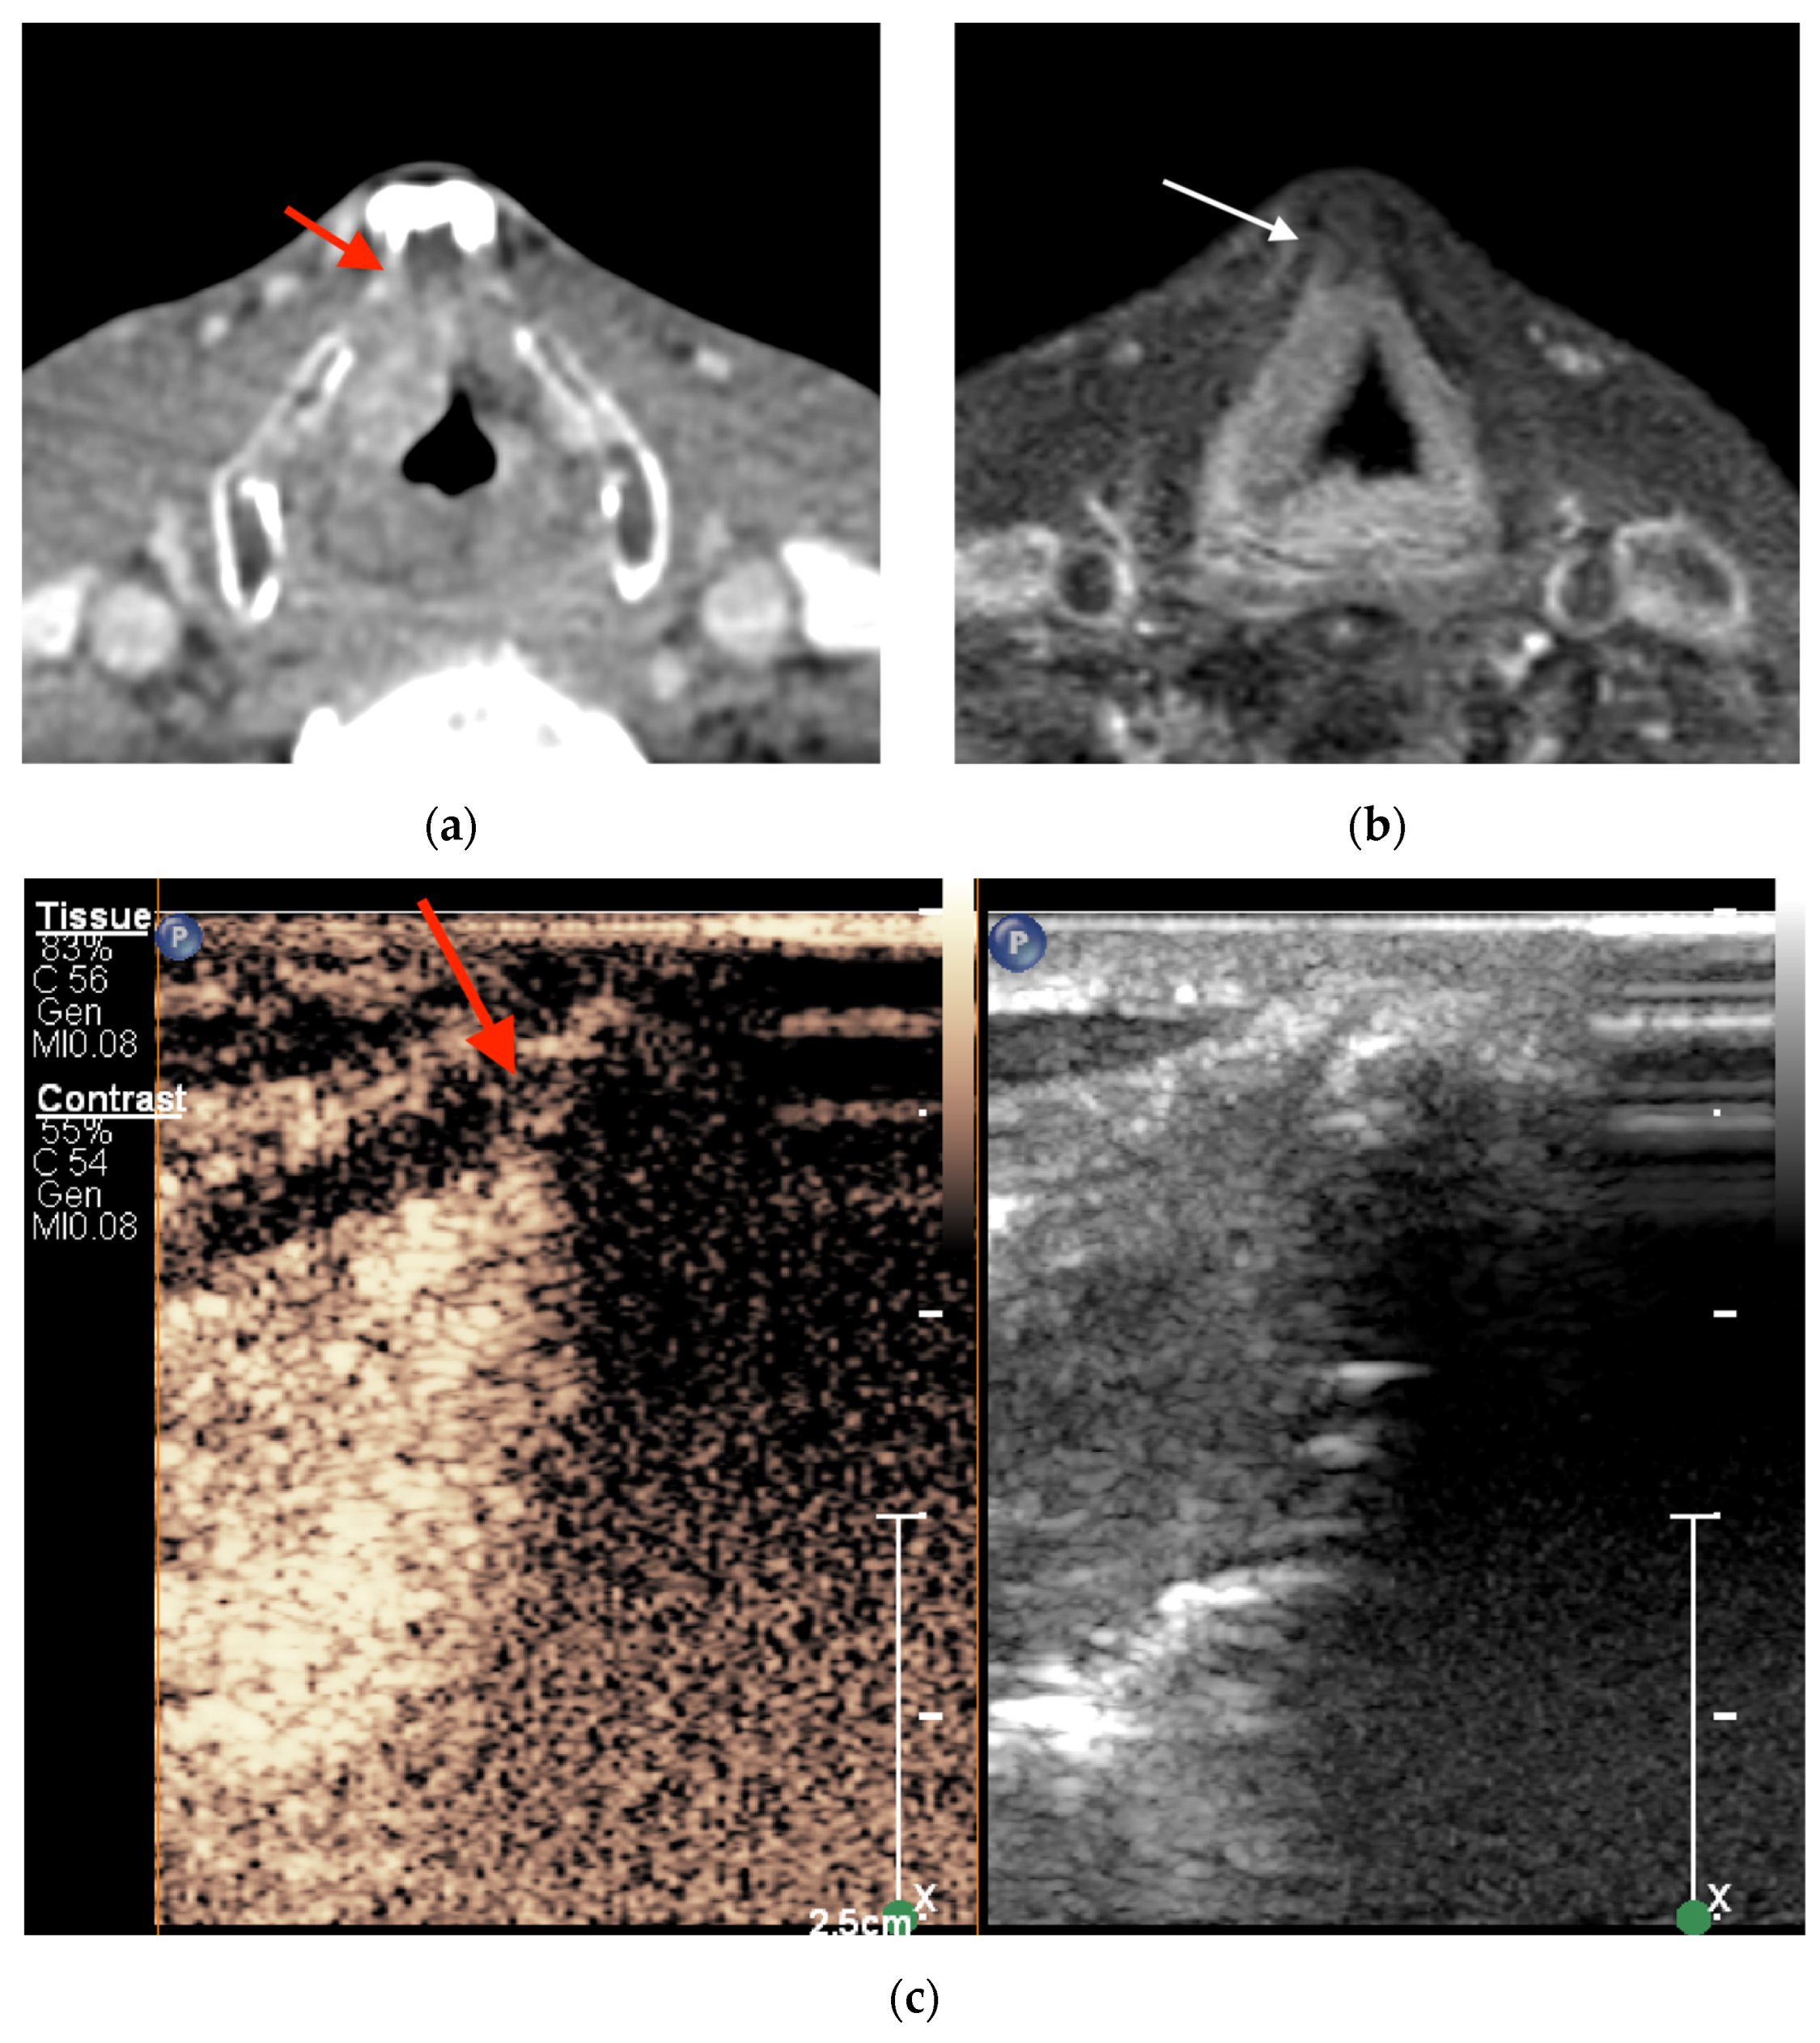

1. Introduction

2. Materials and Methods